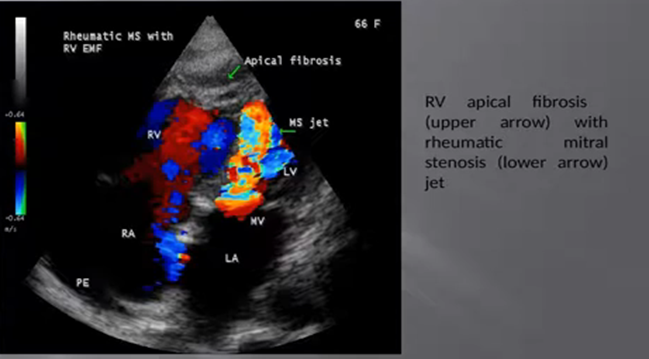

RF (Rheumatic fever and EMF may coexist in the same patient as shown in Figures 46 & 47.

Figure 47 showing RV apical fibrosis (upper arrow) and rheumatic mitral stenosis (lower arrow) [60]